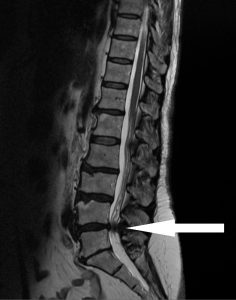

Rentgenové vyšetření hrudní a bederní páteře.

- Úsek MRI - magnetická rezonance

Charakteristika a princip metody

Vyšetření pomocí magnetické rezonance (MR) patří mezi moderní zobrazovací metody. Vyniká především vynikajícím kontrastním rozlišením jednotlivých tkání, tj. schopností odlišit od sebe i tkáně s velmi obdobnou strukturou. V praxi to znamená nejen například vynikající odlišení bílé a šedé hmoty mozkové, ale (a to je důležitější) rozlišení normální tkáně od tkáně postižené chorobným procesem. V tomto ohledu má magnetická rezonance výsadní postavení mezi všemi zobrazovacími metodami.

Využití MR je velmi široké, od klasického zobrazení centrální nervové soustavy po zobrazení cév (MR angiografie), kloubů, orgánů hrudníku (srdce) a břicha či další speciální techniky jako MR spektroskopie, funkční MR mozku, MR zobrazení difůze atd.

Přístrojové vybavení a ukázkové snímky: